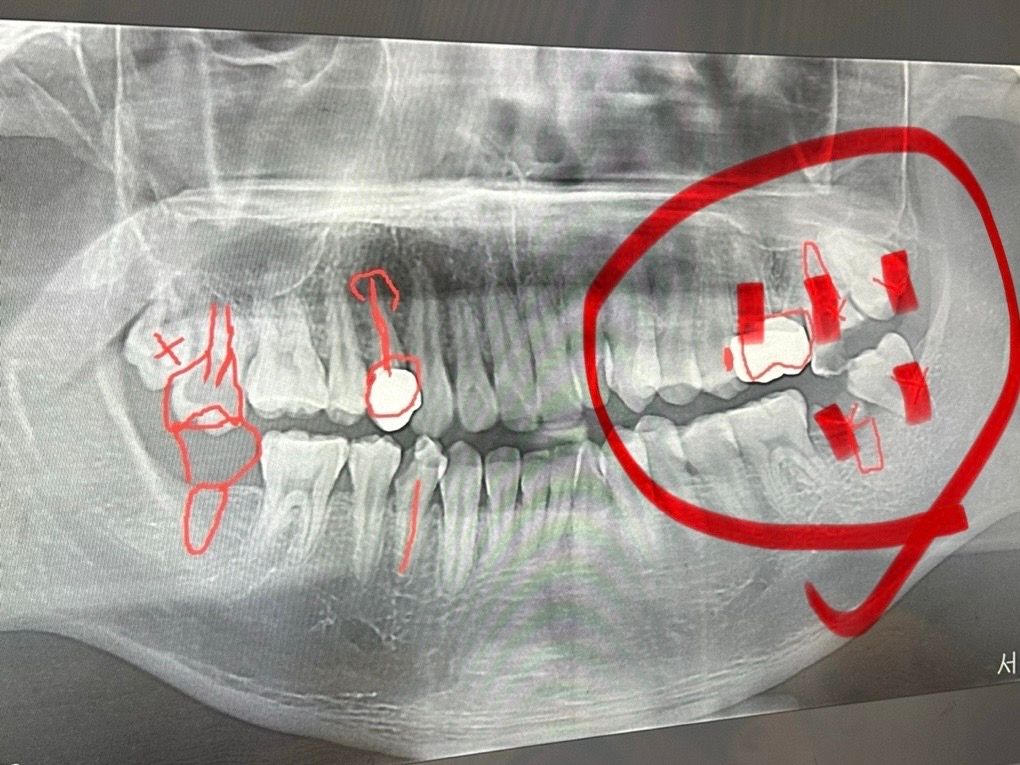

좌측 어금니 3개, 사랑니 2개 동시발치 및 임플란트 즉시 식립(3개, 어금니) 진행

다음주에 치과에서 좌측 어금니3개와 사랑니 2개를 한번에 발치하고, 어금니 발치한 자리에는 임플란트 나사를 즉시식립(3개)한다고 합니다.

오른쪽 동그라미 친 부분들 입니다 :)

• 1번 째 사진